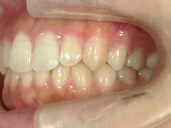

矯正歯科 治療後 右

矯正歯科 治療後 左